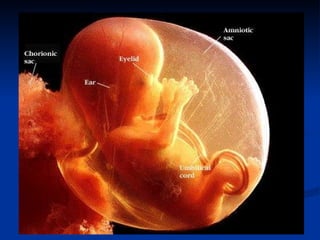

The document discusses embryonic development in humans. It begins with fertilization and cleavage, followed by gastrulation where the three germ layers are formed. During this time the primitive streak and Henson's node develop. Organogenesis then occurs, forming individual organs from the germ layers. Mammalian development includes the allantois and notochord. In humans, the placenta forms and gestation occurs over three trimesters, with major organ structures present by the first trimester.